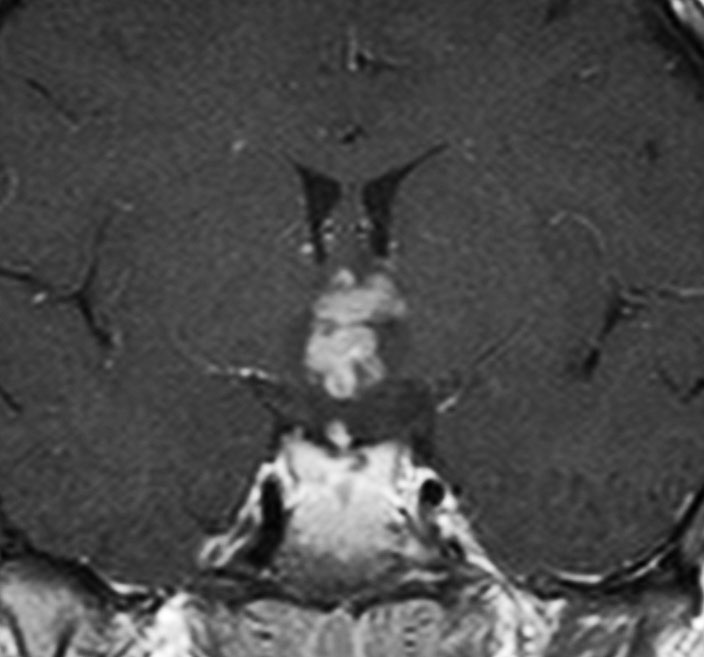

血清HCG-beta 4.5mIUで,下のMRIに見られるように第3脳室(視床下部)のグリオーマ(毛様細胞性星細胞腫)と見間違うような腫瘍でした。下垂体柄は太くなっていないし下垂体のサイズも普通です。もちろん水頭症もありませんので,開頭手術で生検をしてgerminomaの診断を得ました。

上のMRIで視神経交叉が腫大しているのが解りますが,下のMRI CISS画像では更に明らかです,左右の視神経と視交差と視索が腫大していました。視力を計ったら,右0.6,左1.5でいびつな視野欠損がありました。腫瘍はのう胞形成しながら左の視床下部から大脳基底核にも浸潤していました。